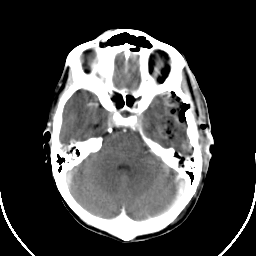

Metastatic bronchogenic carcinoma: Roentgen-ray CT (post-op) -- Slice #6

[Home][Help][Clinical] Slice 6